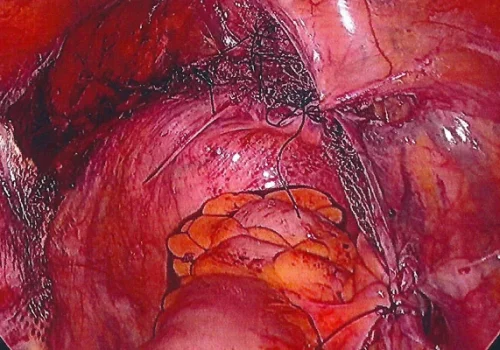

Procedure

She subsequently underwent Total Laparoscopic Hysterectomy and Laparoscopic Mesh Sacral Colposuspension.